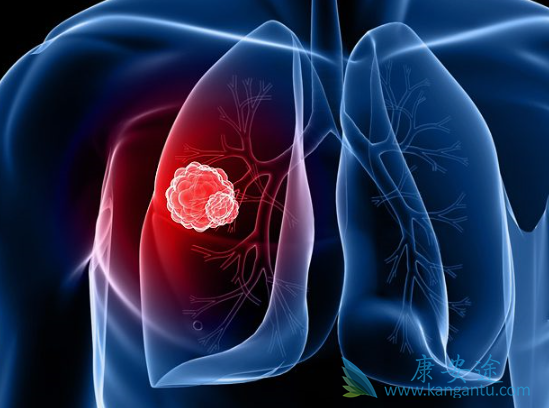

对于晚期肺癌患者,目前除了放化疗外,靶向药物治疗的地位越来越重要,虽然靶向药物的副作用比传统的放化疗轻,但是在应用靶向药物时仍不能大意,肺癌晚期吃靶向药常见的副作用如下几方面。1)过敏反应。对于肺癌常用的靶向药来说,这种症状是比较少见的,一般多见于单克隆抗体类的靶向药物如美罗华、爱必妥和阿瓦斯汀等。

2)皮肤毒性。这是肺癌靶向药最常见的毒副作用,主要表现为指甲改变、甲沟炎、口腔溃疡、皮疹等,预防甲沟炎及皮疹。3)消化道毒性。腹泻和呕吐是等消化道反应也是较为常见的,尤其是腹泻,轻度的腹泻可不用处理,注意注意少食辛辣刺激性的东西和生冷寒凉之品,寒凉之品容易伤及脾胃而引起腹泻。

4)肺毒性。肺毒性主要包括亚急性肺炎和急性肺炎、肺出血、咯血、肺动脉高压等。最具有代表的靶向药物就是易瑞沙和特罗凯,使用后有可能引起肺炎,主要表现为呼吸困难、咳嗽和发热,轻者可观察,症状明显则须停药并到医院治疗。5)肝功能损伤。最常见的就是转氨酶升高,尤其谷草转氨酶升高。